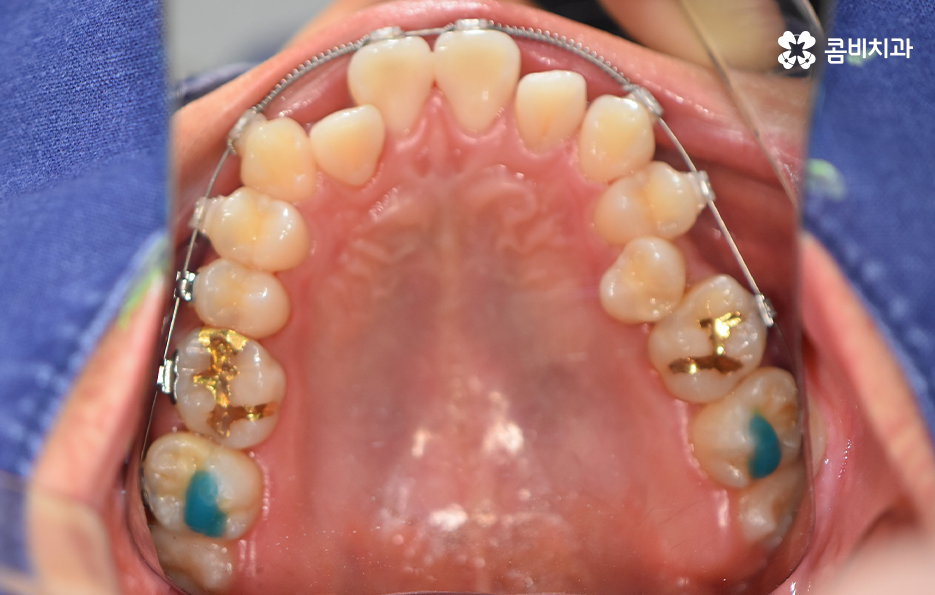

오늘 포스팅에서 보여지는 사진에서는 비발치 교정으로 덧니 교정이 가능했던 사례입니다. 덧니 교정 사례에서 발치교정 케이스는 흔한 치료 방법이긴 하지만 발치에 대한 판단은 치열만이 아니라 골격과 얼굴형을 종합적으로 고려하여 판단하고 치아를 얼마나 이동시켜야 할지 예측하여 판단하기 때문에 3D CT 등의 첨단 장비를 통한 검진과 경험 많은 교정 전문의와 충분히 상의하고 결정해야 합니다

종합하면 발치교정의 필요성은 얼굴과의 조화, 골격 그리고 교합 등을 전체적으로 고려하여 판단하기 때문에 각 환자분들이 필요한 치아의 이동 정도를 정확히 예측하고 필요한 치아 이동 공간을 확보함에 있어서 발치교정이 적합할지 아니면 비발치적인 방법으로도 치아 이동 공간이 확보 가능한지 따져보고 있으며 발치교정이 아니더라도 치간삭제, 악궁확장, 어금니 후방이동과 같은 방법으로 공간 확보가 가능하기 때문에 각 환자분들에게 적합한 1:1 맞춤형 치료가 진행되고 있어요